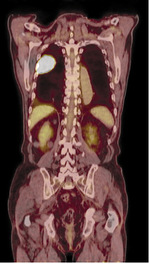

Ryc. 1. Badanie PET-CT po podaniu 18FDG. Zmiany przerzutowe do wątroby w przebiegu raka jelita grubego.

Techniki radioizotopowe dają ogromne możliwości. W odróżnieniu od innych metod pozwalają na charakterystykę procesu chorobowego w kategoriach czynnościowych. To ich wielka zaleta, która umożliwia wczesne rozpoznanie schorzeń, określenie stopnia zaawansowania choroby i obserwowanie postępów leczenia (ryc. 1-2).